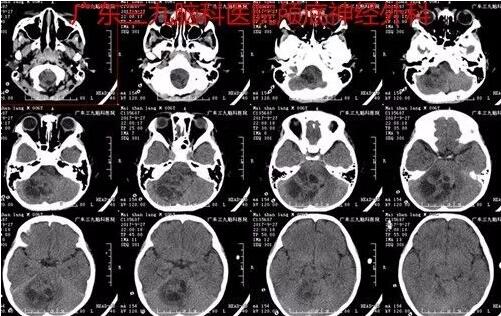

图1:2017-09-27术前CT示右侧小脑半球一团片状等、低混杂密度影,边界不清,大小约53mm×48mm,邻近四脑室受压变窄。